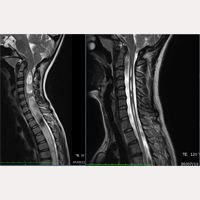

Skolioza idiopatyczna

Od 20 października 1993 do listopada 2016 techniką Sekcji Filum Terminale, stosując FILUM-SYSTEM®, zoperowaliśmy ponad 1000 pacjentów cierpiących na Syndrom Nerwowo-Czaszkowo-Kręgowy i/albo Chorobę Filum z Syndromem Arnolda Chiari I, Jamistością rdzenia i Skoliozą.